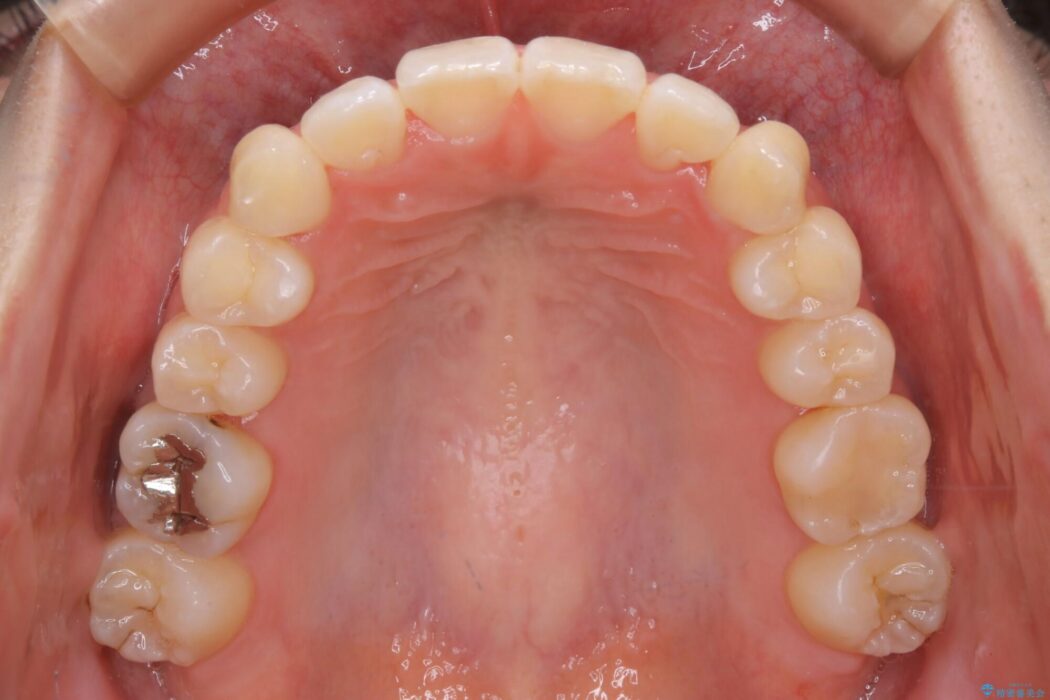

治療前と治療後を見比べると口元の見た目の変化が良く分かります。

本症例では奥歯から順に移動させるため前歯の変化を感じるには時間が掛かりましたが、インビザライン装置とマイクロインプラントを併用することで健康な歯を抜歯することなく歯列をきれいに整えることができました。